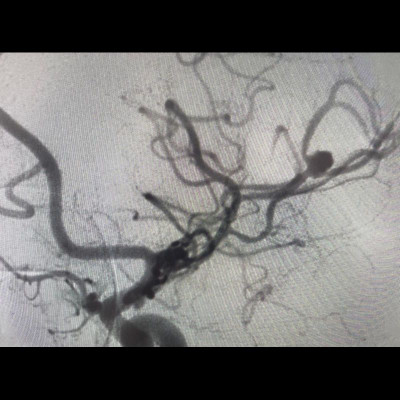

- DSA görüntülemede (G) sol MCA M2 segmentinde anevrizmatik dolum fazlalığı izleniyor (ok). Bu anevrizmaya eş zamanlı koil işlemi yapılıyor (oklar) ve işlem sonrası kontrol BT anjiografi görüntüsünde (H) metalik koil materyali izleniyor (ok).